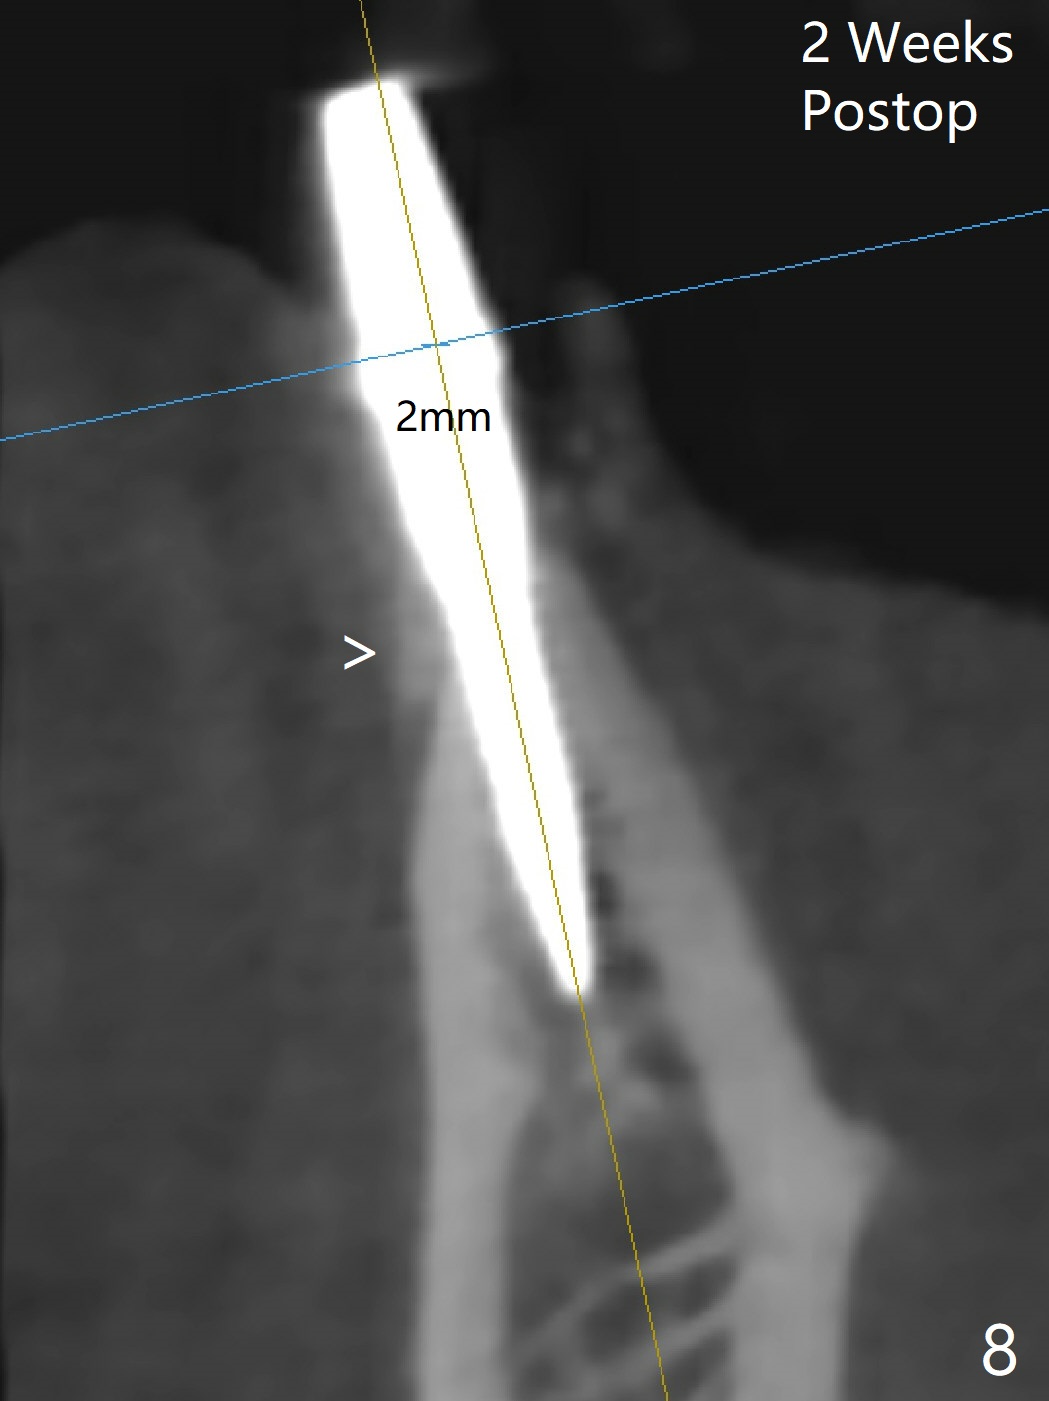

After removing #23-26 FPD and the 3x14 mm 1-piece implant at #26 (Fig.1,2 *), a new osteotomy is initiated in the narrow ridge (after ridge top reduction) approximately at #25 (Fig.2 <). Following placement a 2x10(4) mm implant at #25 (Fig.3-5) and Osteogen plug in the osteotomy at #26, Vanilla graft is placed around the implant, especially buccal. Periodontal dressing is applied after suturing. The buccal and lingual flaps are erythermatous and edematous without pain 8 days postop (Fig.6). The wound seems to be healing 2 weeks postop (Fig.7), no sign of osteonecrosis. With placement of a 2 mm implant at #25 (Fig.8 (>: bone graft buccally)), the buccal plate remains normal in thickness. When a 3 mm implant is placed at #23 (Fig.9), approximately 4 threads appear to be exposed (between arrowheads), partially due to the thick lingual plate (*).